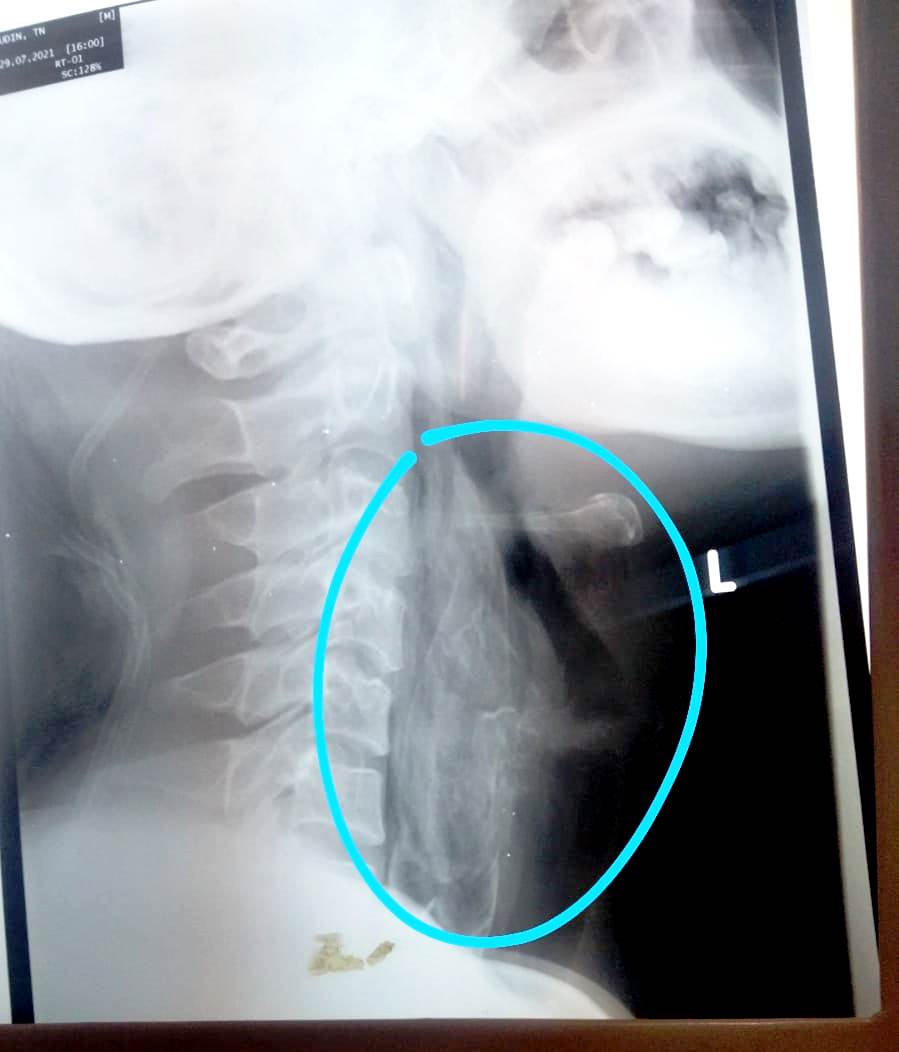

Setelah dilakukan rontgen, ternyata ikan tersebut cukup besar dan duri-durinya sudah menyangkut di dinding tenggorokan.

“Kita coba semaksimal mungkin mengeluarkan ikan tersebut. Memang pada saat buka mulut, bagian ekor ikan tersebut keliatan, namun setelah sekitar lima kali dilakukan percobaan untuk mengeluarkan ikan tersebut, terlalu berisiko,” ungkapnya.

Ikan tersebut juga tidak mungkin untuk ditelan atau diteruskan ke saluran cerna karena cukup besar, dan berpotensi tersedak, sehingga berpotensi pula mengganggu pernafasan.